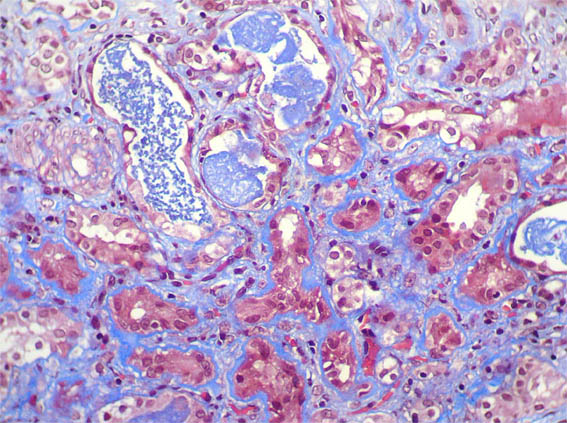

Figure 4.

Masson's

trichrome stain,

X400.